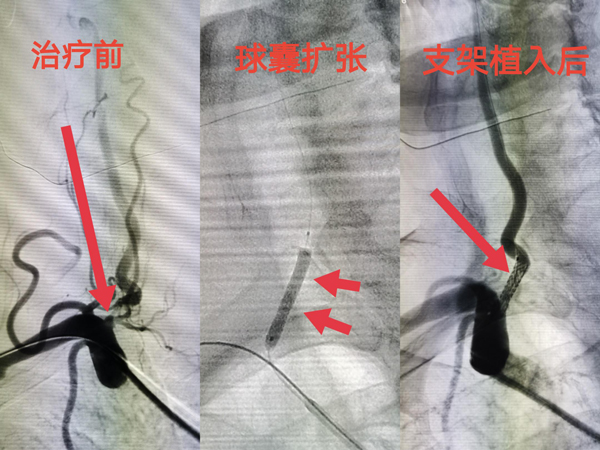

65岁男性患者,以发作性头晕不适1周入院。入院后彩超提示右侧主动脉起始段狭窄,左侧椎动脉纤细。进一步行全脑血管造影术明确右侧椎动脉起始段高度狭窄。随后行右侧椎动脉球囊扩张术+支架植入术,术后血管狭窄完美解除,患者头晕症状明显改善。